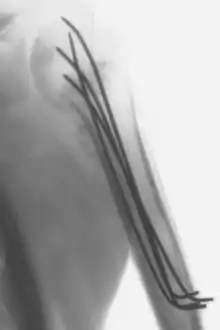

Intraoperative X-ray of a humerus fixated by Kirschner wires